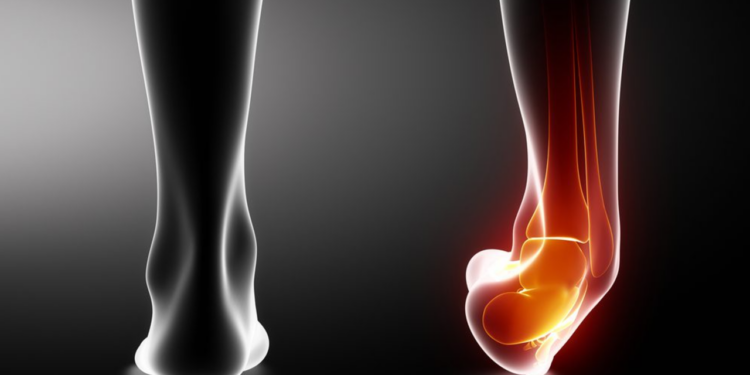

A torção no tornozelo ocorre quando os ligamentos são esticados além do limite, causando dor, inchaço e instabilidade, e em casos graves pode haver ruptura necessitando acompanhamento médico.